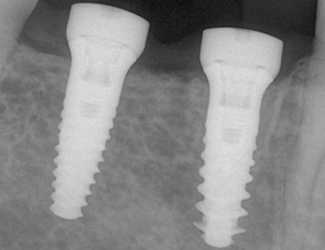

Implantatbehandling ble utført med: Straumann TLX SLActive 4,5 × 10 mm RT i region 45 og Straumann TLC SLActive 4,5 × 10 mm RT i region 46.

Implantatene ble installert med et innsettingsmoment på 45 Ncm. Ved initial ISQ-måling viste begge implantatene en verdi på 79, noe som indikerte god primær stabilitet. Etter åtte ukers tilheling ble implantatene vurdert som stabile for avtrykkstaking før permanent protetisk rehabilitering, med en målt ISQ-verdi på 88.

2. Implantatinstallasjon region 45 & 46.